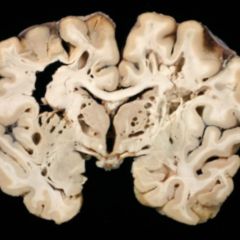

Bei Subarachnoidalblutungen tritt Blut in den Subarachnoidalraum ein, wo es sich vor allem in den Zisternen ansammelt.